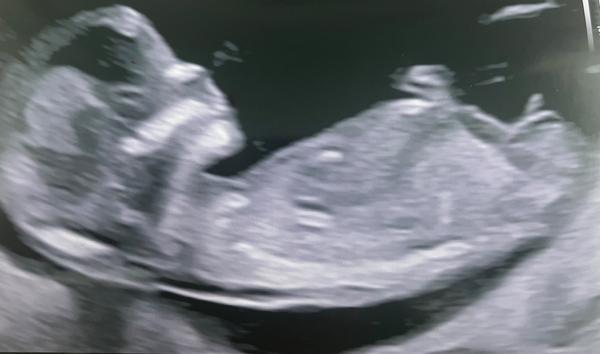

Holka nebo kluk?

Ahoj, je mi jasný že víc mi řekne doktor a 100%to bude až vytlačím, přesto by mě zajímaly vaše tipy 😀😀 tak snad se do mě hned někdo neobuje. Ano důležité je aby bylo mímo zdravé a co to bude neovlivnim. Ale ta ženská zvědavost je k zbláznění 🙈😅

Taky bych řekla kluk, pokud je teda to podle čeho to tipuji pohlavní hrbolek :D

@andelina2004 pohlavni pahrbek je vzhuru, je to kluk

@takaya aha, ja mam totiz pocit, že to co tam trčí je nožička 😅 prsty u nohy, protoze ma pokrčenou nohu 😅🤷♀️ale co já vím

Taky tipuju kluka. Jestli z tohoto bude holka, sním svůj klobouk 😀 Syn měl stejný hrbolek, holka naopak jinak směřovaný.

Z tohoto snimku nejde moc poznat co je to za pohlavi. To co tam zdanlive vypada jako pohlavni hrbolek jsou spise prsty. Takze to na tuty bude holka 🤣

@andelina2004 ahojky , tak přesně takhle jsem tom měla na prvním screeningu a doktor mi řekl na 70 % kluk,ale já jsem musela kvůli věku podstoupit krevní testy (genetika) a v 5 nebo 6 měsíci byla potvrzena holčička .